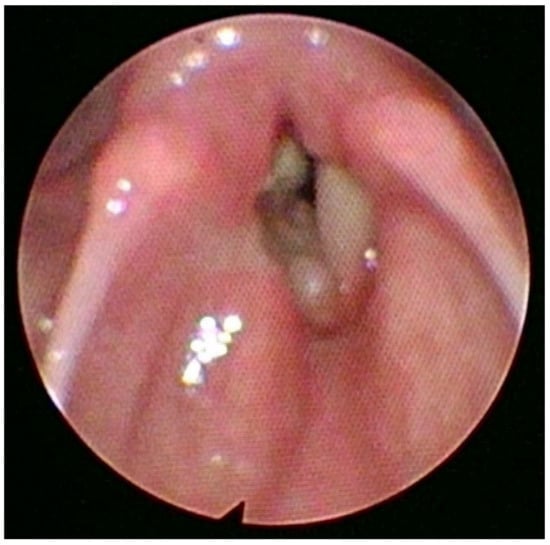

Endoscopic view of the larynx showing the lesion. The adenoid cystic carcinoma (ACC) arises from the minor salivary glands. It accounts for 1–5% of all head and neck malignancies. Since the minor salivary glands are present in small amounts throughout the larynx, the laryngeal adenoid cystic carcinoma is sporadic, representing less than 1% of all laryngeal malignancies [1]. Regarding the onset of laryngeal ACC (LACC), the prevalent age ranges from 50 to 60 years. However, younger generations can be affected, and both sexes are equally affected, with a slight male predominance and a male-to-female ratio of 1,5:1. There is no evidence connecting LACC etiology with smoking. An early perineural and hematological spread make this kind of carcinoma liable for local recurrence and distant metastasis, especially to the lung. Therefore, is important to increase the frequency of controls during follow-up [2]. Laryngeal ACC can originate from any part of the larynx. The most common origin is the subglottic area (64%), followed by the supraglottic area (25%), the glottic area (5%), and the trans-glottic area (6%) [3,4]. The clinical presentation is usually variable and related to the lesion location [5,6,7]. In November 2021, a 70-year-old no-smoker female patient presented to our hospital’s emergency department with stridor, severe dyspnea at rest, and hoarseness of voice. The O2 saturation level was 87% on air without cyanosis. An endoscopic laryngeal examination revealed bilateral vocal cord paralysis in adduction. Firstly, the patient underwent an urgent tracheostomy under general anesthesia. The procedure also included a laryngeal examination (micro-laryngeal surgery) under general anesthesia with tumor mapping, which revealed a bilateral mucosal thickening of the anterior thirds and anterior commissures of both vocal folds and a right vocal fold submucosal thickening (Figure 1). Multiple biopsies from different laryngeal areas were taken for histopathological examination. The pathological tissue revealed the presence of an adenoid cystic carcinoma of the solid type associated with the immunophenotype CK AE1 AE3 +, CD117+, CK7+/−, p63 +/−, p40+/−, Vimentin +/−, SMA+/−, S100+/−. Then, the patient underwent a CT scan of the neck chest and brain with a contrast medium and an abdominal ultrasound examination. The first chest, brain, and abdominal radiological evaluations did not show metastatic lesions. The neck CT scan revealed the presence of small submucosal bilateral glottic masses, associated with increased cervical lymph nodes volume, without subglottic and extra-laryngeal extensions (Figure 2).